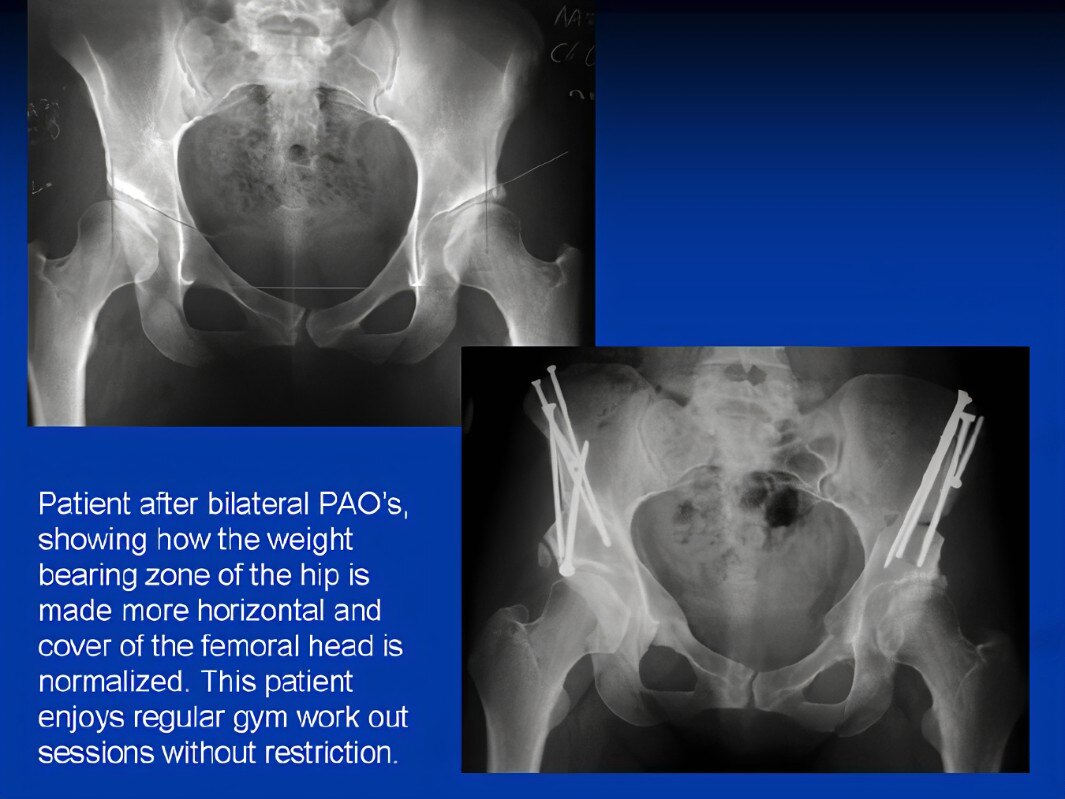

(6) 保髋截骨手术:主要有PAO截骨、ITO经转子间截骨等。

髋臼发育不良患者在PAO截骨术前,术后的X线片

另外,不是所有患者都需要全髋关节置换手术治疗。目前,国内外主流的学者观点认为,保髋截骨手术是纠正青壮年髋臼发育不良(先髋,DDH)髋关节骨骼结构畸形,显著改善髋关节疼痛不适、活动受限、跛行等最好的治疗方式。